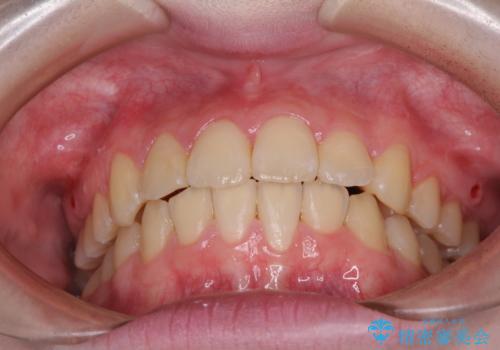

- 上下前歯のデコボコを気にして来院された患者様です。

前歯の叢生は強かったのですが、口元が引っ込んでいる印象であったため、非抜歯にて矯正治療を行うこととしました。